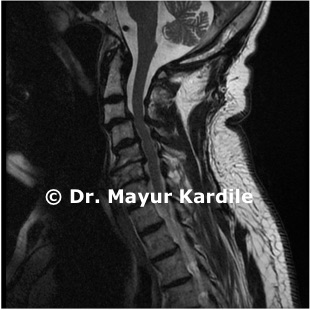

• Clinical examination: Neurological examination including assessment of hand function, reflexes, gait, and balance • MRI of the cervical spine: Gold standard for diagnosis — shows cord compression, disc herniations, spinal canal narrowing, and signal changes in the cord • CT myelogram: In patients unable to undergo MRI • X-rays: To assess cervical alignment and detect instability • EMG/NCV: To differentiate from peripheral nerve conditions

Case Images